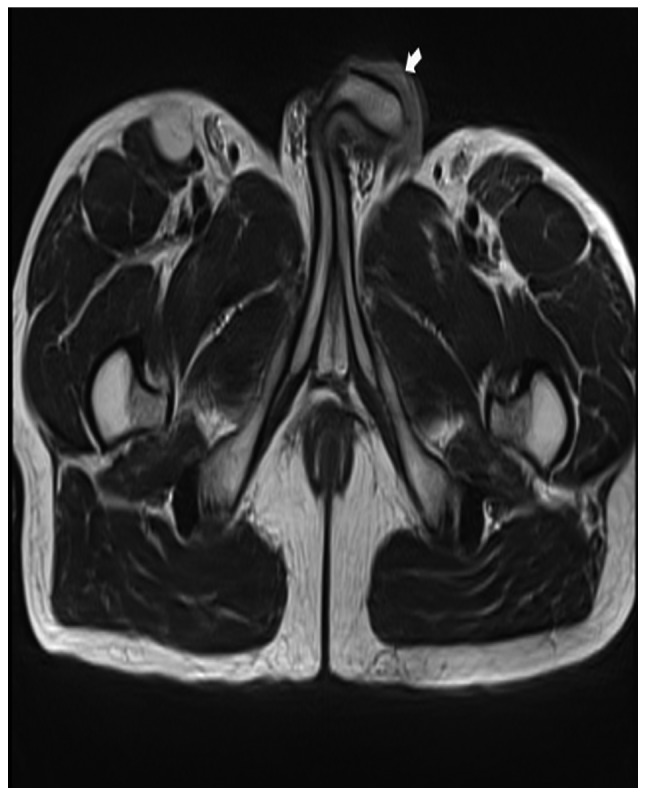

The first postoperative visit was conducted on day 39 following surgery, the patient presented with a painful swelling over the glans penis and purulent discharge of the urethra. On examination, the glans penis was stiff and there was a ~5-mm nodular lesion on the distal aspect of the penile shaft. Pelvic magnetic resonance imaging (MRI) revealed a lesion with an unclear boundary measuring 0.6 cm in diameter (Fig. 3). A biopsy was performed and histopathology indicated squamous atypia and suspected squamous cell carcinoma. Finally, the patient consented to a partial penectomy and histopathology revealed a well differentiated squamous cell carcinoma (Fig. 4). A six-month postoperative follow-up was conducted and the patient was able to urinate whilst standing and the IIEF-5 score was 15 (moderate). Follow-up of the patient is ongoing.

Figure 3.

Magnetic resonance image of the pelvis. The white arrow indicates the abnormal lesion.

The European Association of Urology guidelines on penile cancer classify penile cutaneous horn as a premalignant lesion (8) and approximately one-third of penile cutaneous horns are associated with an underlying malignancy (2). It has previously been reported that MRI is helpful when there is uncertainty regarding the depth of infiltration or proximal extension (9). When the patient in the present case was hospitalized for the second time, a physical examination presented a nodular lesion on the distal aspect of the penile shaft and the MRI result provided the basis of the nature of the lesion.